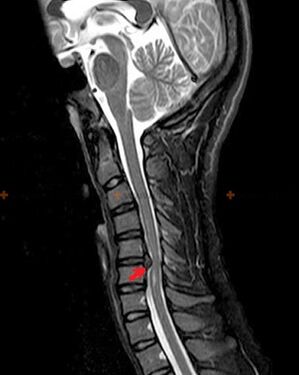

Osteokondrozu teşhis etmek için aşağıdaki araştırma yöntemleri kullanılır: radyografi (tercihen fonksiyonel testlerle), MSCT ve MRI. İkinci çalışma, omurlararası yapıların durumunun çok net bir şekilde görselleştirilmesine izin vermesi nedeniyle en çok tercih edilendir.

Yukarıda açıklanan değişikliklerin yanı sıra, MSCT ve MRI tarafından tespit edilen intervertebral diskin yapısındaki değişiklikler, osteokondrozun varlığını doğrulayan güvenilir işaretler olarak hizmet eder.